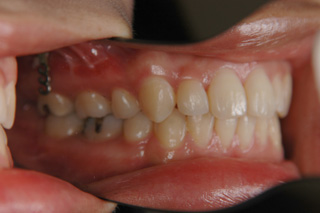

(上下顎前突/上下顎小臼歯抜歯)

装置撤去です。動的処置は2年弱でしたので、歯の移動させた距離で考慮すると、比較的短い治療期間でした。極めてよい咬合状態が得られたと思います。いずれも強い固定源を利用した結果の成果と考えられます。まだ、オーソアンカー SMAPシステム がそのまま残っているのが見えますが、もう必要ないので撤去して貰う予定です。今後は保定治療に移行し、数年にわたって咬合の安定状態を管理していきます。